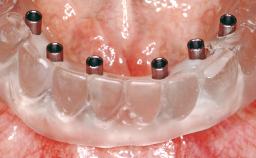

A 56-year-old female patient was referred to the clinic because of retention problems with her mandibular denture. She had been completely edentulous for more than 33 years and wore her sixth set of complete conventional dentures, which had been delivered 5 years previously. An oral surgeon had performed a vestibuloplasty in the interforaminal region of the mandible with a piece of skin tissue 12 years earlier. The panoramic radiograph and lateral cephalometric radiograph exhibited the hypotrophy of the inferior alveolar process. The mandible was a Cawood class VI,and the height of the mandible in the interforaminal zone was 15 mm.

# of Implants 2

Type of Implants One-Piece

Modality 2 interforaminal implants

Loading Protocol Immediate (bar only)